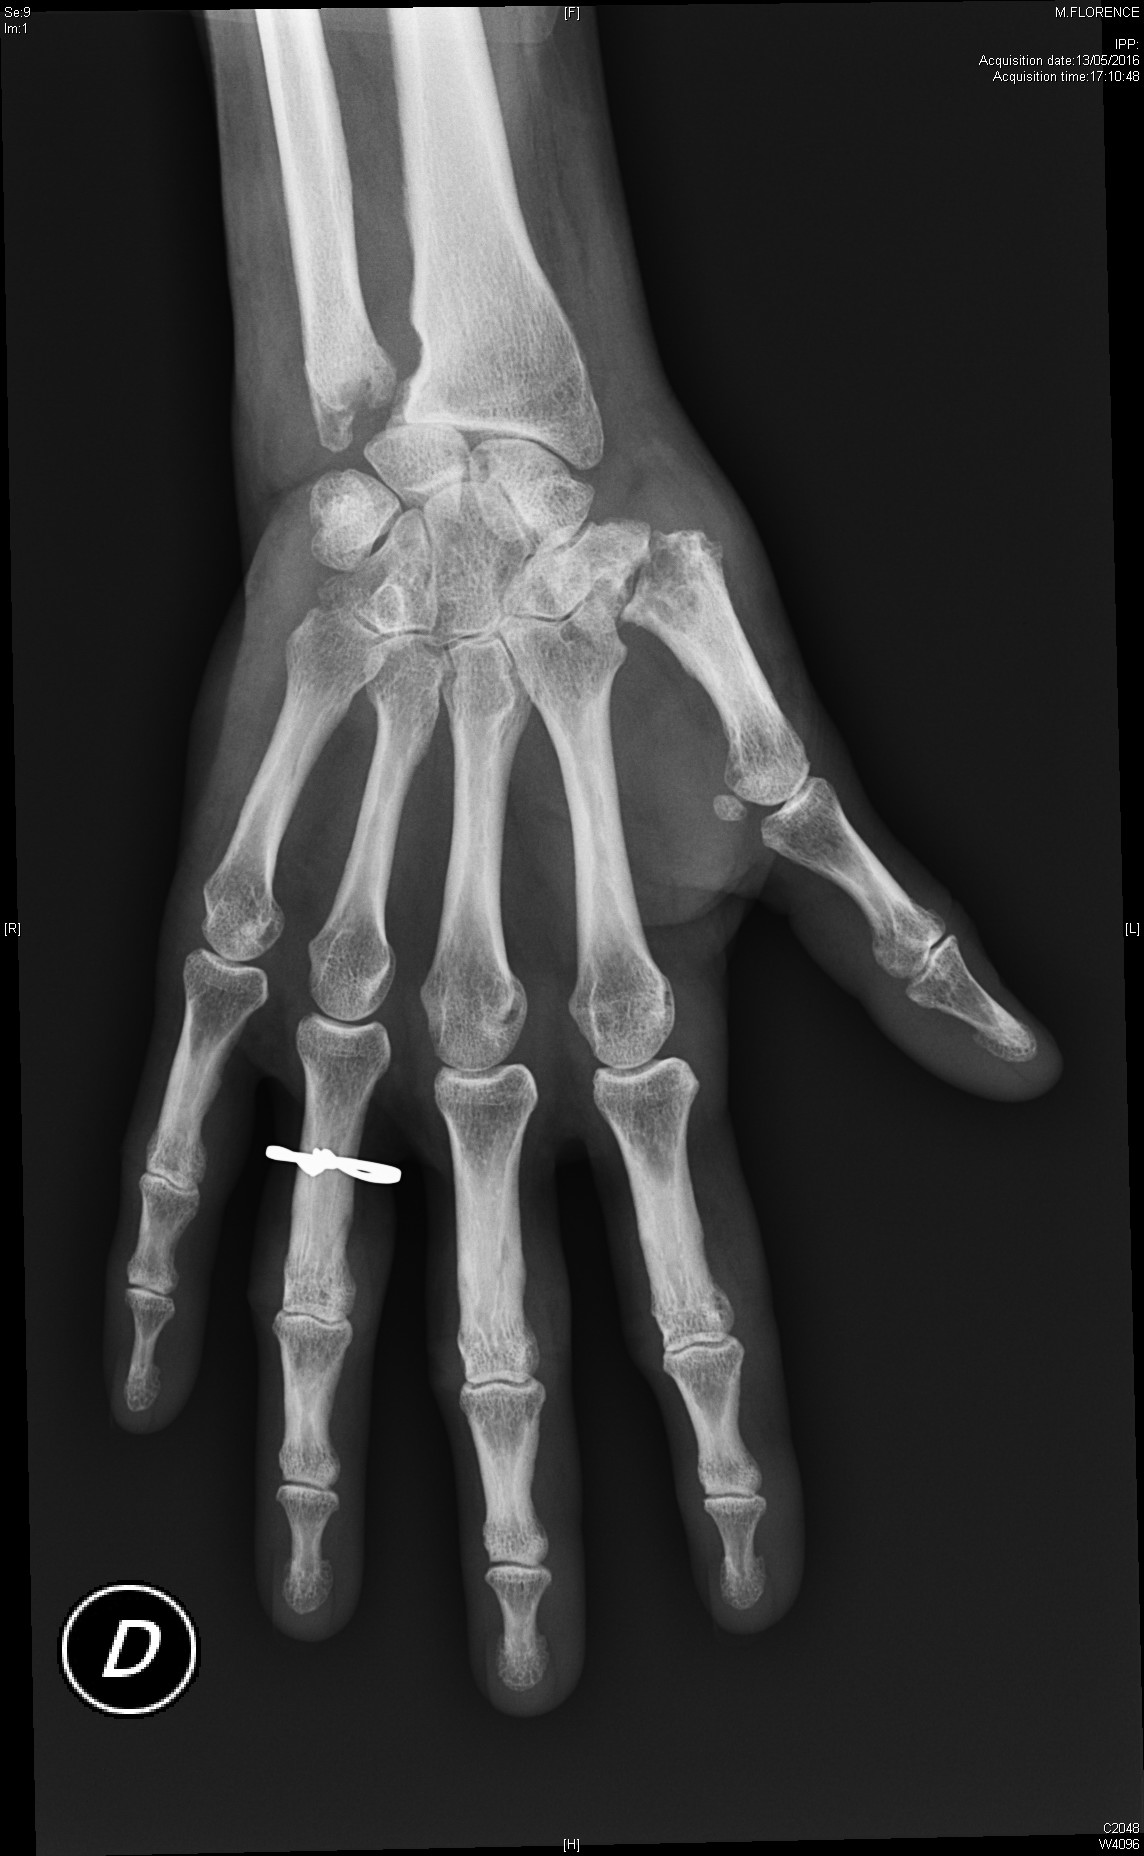

Polyarthrite rhumatoïde débutante, d'emblée érosive

polyarthrite rhumatoïde érosive avec signe de Freiberg radiographique au poignet